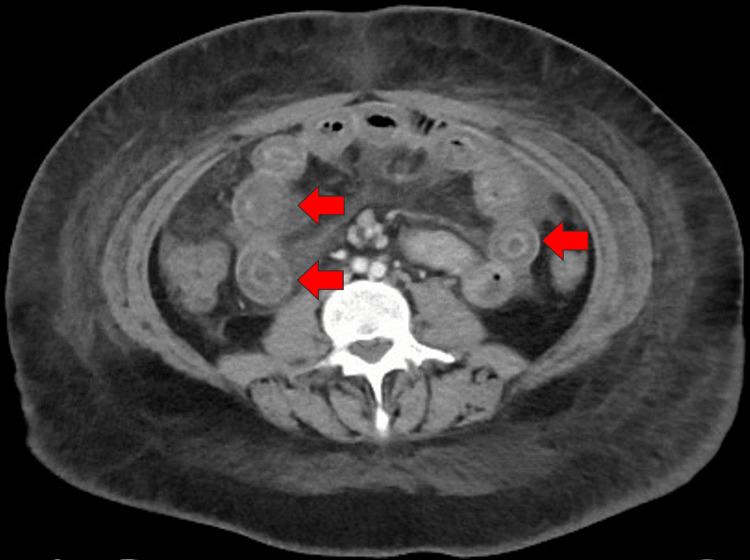

Lupus enteritis (LE) is an uncommon cause of abdominal pain in individuals with systemic lupus erythematosus (SLE). This condition is explained by the inflammation of the intestinal wall caused by the accumulation of immune complexes and activation of the complement system. A 19-year-old previously healthy Kuwaiti woman arrived at the emergency department (ED) complaining of diffuse abdominal pain, non-bloody diarrhea, and nausea. The symptoms started two days before presentation. The patient described the abdominal pain as sudden, sharp, and stabbing in nature, with a severity of 10 out of 10, and mainly located in the suprapubic area. On examination, the patient's vital signs were normal. She had no skin rash, oral ulcers, arthritis, or palpable lymphadenopathy. Her abdomen was soft on palpation, with diffuse tenderness. Her initial laboratory investigations showed a normal hemoglobin level and WBC count but lymphopenia (0.6 x 10/L; normal, 1-3 x 10/L). A computed tomography (CT) scan of the abdomen showed small bowel loops with diffuse edematous wall thickening with target signs. The descending and sigmoid colon, and the rectum walls were also thickened and edematous. Significant pericolonic fat stranding and free fluid with preserved enhancement suggested an active systemic inflammatory process. Anti-nuclear antibody and anti-double stranded DNA antibody test results were positive. Acute abdominal pain was managed with IV corticosteroids, and 10 mg/kg IV belimumab was initiated. The patient was followed up in OPD after one, three, and six months, where she did not mention any relapse of LE nor any side effects from belimumab. The diagnosis of LE in this case was challenging because of the absence of a prior diagnosis of SLE. Clinical manifestations of this condition, which include abdominal discomfort, vomiting, and diarrhea, are non-specific and can be mistaken for several chronic gastrointestinal disorders, posing a diagnostic problem. Although belimumab is not commonly used to treat LE, we were able to successfully manage the patient using it, making it a promising new method for treating LE.

狼疮性肠炎(LE)是系统性红斑狼疮(SLE)患者腹痛的罕见原因。这种情况是由免疫复合物的积累和补体系统的激活导致肠壁炎症所解释的。一名19岁、此前健康的科威特女性因弥漫性腹痛、非血性腹泻和恶心来到急诊科(ED)。症状在就诊前两天开始。患者将腹痛描述为突发性、尖锐性和刺痛性,严重程度为10分(满分10分),主要位于耻骨上区域。检查时,患者生命体征正常。她没有皮疹、口腔溃疡、关节炎或可触及的淋巴结肿大。触诊时她的腹部柔软,有弥漫性压痛。她最初的实验室检查显示血红蛋白水平和白细胞计数正常,但淋巴细胞减少(0.6×10⁹/L;正常范围为1 - 3×10⁹/L)。腹部计算机断层扫描(CT)显示小肠肠袢肠壁弥漫性水肿增厚,呈靶征。降结肠、乙状结肠和直肠壁也增厚且水肿。结肠周围明显的脂肪条索影和游离液体且强化良好提示存在活跃的全身炎症过程。抗核抗体和抗双链DNA抗体检测结果呈阳性。急性腹痛采用静脉注射皮质类固醇进行治疗,并开始静脉注射10mg/kg贝利尤单抗。患者在1个月、3个月和6个月后在门诊接受随访,她未提及狼疮性肠炎有任何复发,也未提及贝利尤单抗有任何副作用。由于该患者之前没有系统性红斑狼疮的诊断,所以此次狼疮性肠炎的诊断具有挑战性。这种疾病的临床表现包括腹部不适、呕吐和腹泻,不具有特异性,可能会被误诊为几种慢性胃肠道疾病,从而带来诊断难题。尽管贝利尤单抗通常不用于治疗狼疮性肠炎,但我们能够成功地用它治疗该患者,使其成为一种有前景的治疗狼疮性肠炎的新方法。